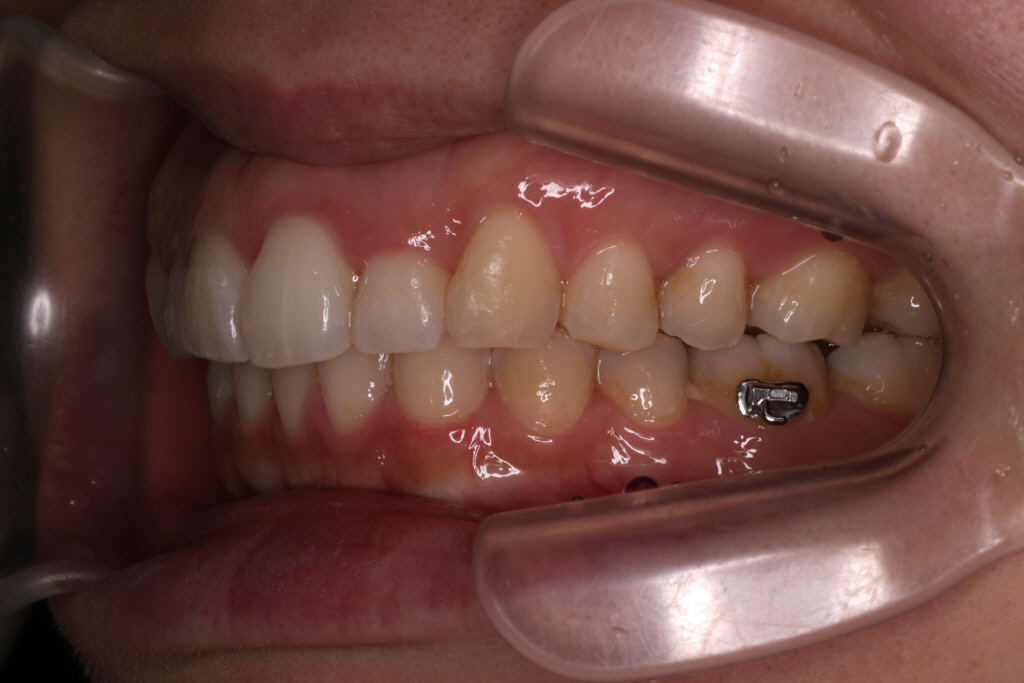

こちらが現在の口腔内写真です。